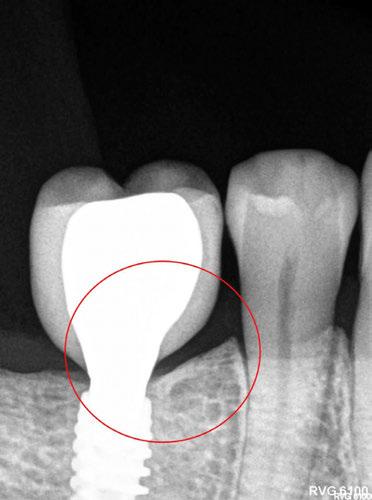

-Estudio radiográfico inicial (ortopantomografía y radiografías periapicales) (Figura 2).

Figura 2. Ortopantomografía inicial.

25, 26, 28, 37, 38, 47 y 48. Presentaba corona desajustada en 13 con extensión en 12, implantes en 35-36, 45-46, con coronas ferulizadas en 35-36, 45-46, y dientes anteriores superiores con enfermedad periodontal Grado IV.